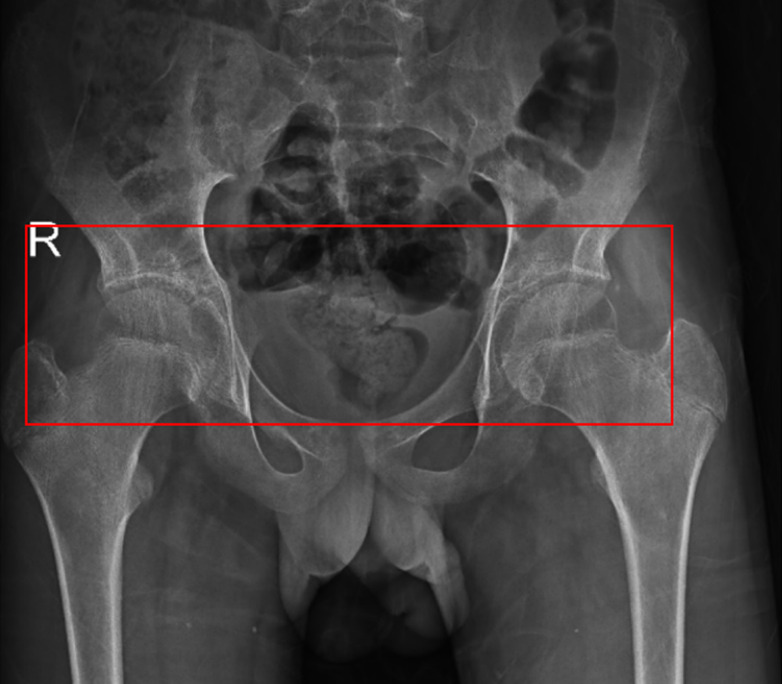

A rare clinical image of a 16-year-old adolescent with juvenile spondyloarthritis.

一个罕见的临床影像的16岁青少年与青少年脊椎关节炎。